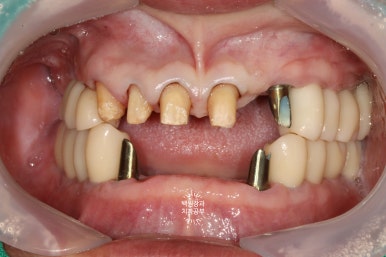

임플란트에 기둥을 연결하고, 임시치아를 붙여 저작 연습을 해봅니다!

임플란트들이 내 잇몸뼈와 잘 결합이 된다면, 이제 슬슬 밥먹는 연습을 해보실 시간입니다.

저는 재활치료라고 표현하는데요... 결국 입은 머리 안에 있는 구조물이고, 상당히 민감하기 때문에 연습을 하면서 익숙해지시는 시간이 필요하지요.

기존에 있었던 모든 임플란트에 맞춤형 지대주 (custom abutment)를 연결해드리고,

상부에 임시치아를 붙여드리게 됩니다.

임시치아는 레진 재질로 되어 있고 (손톱에 하는 네일아트도 레진이죠? 플라스틱입니다.) 왠만한 식사는 레진 치아로 하실 수 있습니다.

임시치아를 붙여드린 뒤 사진입니다.

네개만 남은 앞니도 임시치아로 함께 제작해 드렸어요.

1달 정도 사용 하신 뒤 찍은 사진이라 색상이 조금 좋진 않지만.... 최종보철물은 다를겁니다.!!!

자세히 보시면 임플란트 맞춤형 지대주의 티타늄 색깔이 조금 비춰보이는 곳들이 있네요?

이런 곳들도 세심하게 잡아내어 수정을 해드릴겁니다.

그래도 나름 그럴싸하게 씹을 수 있도록 교합면도 어느 정도 재현해 드린답니다.

슬슬 예쁘게 완성되어가는 느낌이 나시나요?